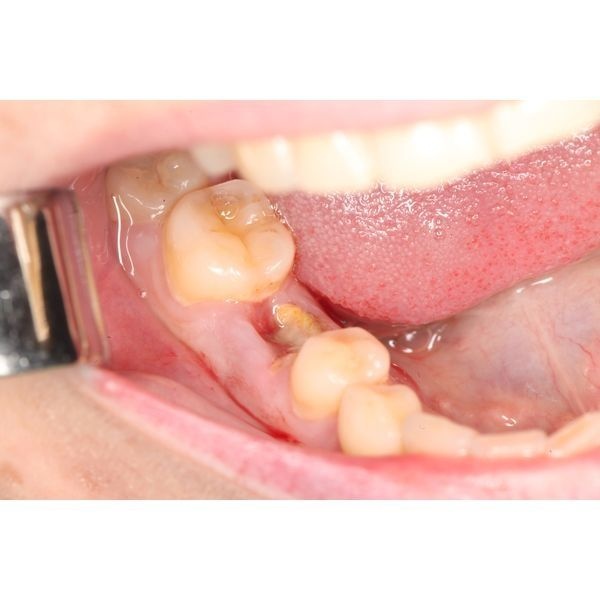

Летом 2022 года в клинику «Евромед» обратился мужчина с разрушенным нижним правым моляром (зубом 4.6).

Пациент жаловался на трудности в жевании и застревание пищи в области повреждённого моляра.

Ранее он неоднократно лечил зуб 4.6 по поводу осложнённого кариеса. Его восстанавливали с помощью штифта и композитного пломбировочного материала.

Более месяца назад коронковая часть разрушилась при пережёвывании жёсткой пищи.

При осмотре полости рта уровень гигиены нормальный, отмечался лишь незначительный пигментированный зубной налёт. Прикус физиологический. Зуб 4.6 разрушен ниже уровня десны, простукивание и зондирование безболезненные. Слизистая в области повреждённого моляра бледно-розовая, без особенностей.

Хронический периодонтит и дефект тканей зуба 4.6.